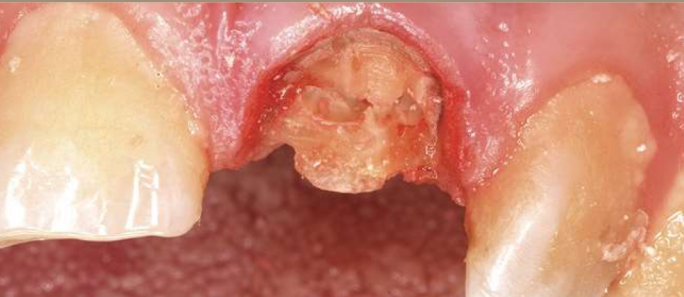

radiographic report

A

21 and 11 - can see fracture on 21

RCT - adequate down to apex and no voids/air bubbles, 11 GP exposed clinically - could expose to bacteria and saliva - inadequate seal - may need redone

Periapical healthy - OK, PDL ligament widening on mesial 21, not PA lesion on 11 as can see PDL going round tooth

what if you saw this toth in a pt about to go into chemo tx and it has previously been RCT

GP exposed risk infection

If fit and healthy - maybe post crown